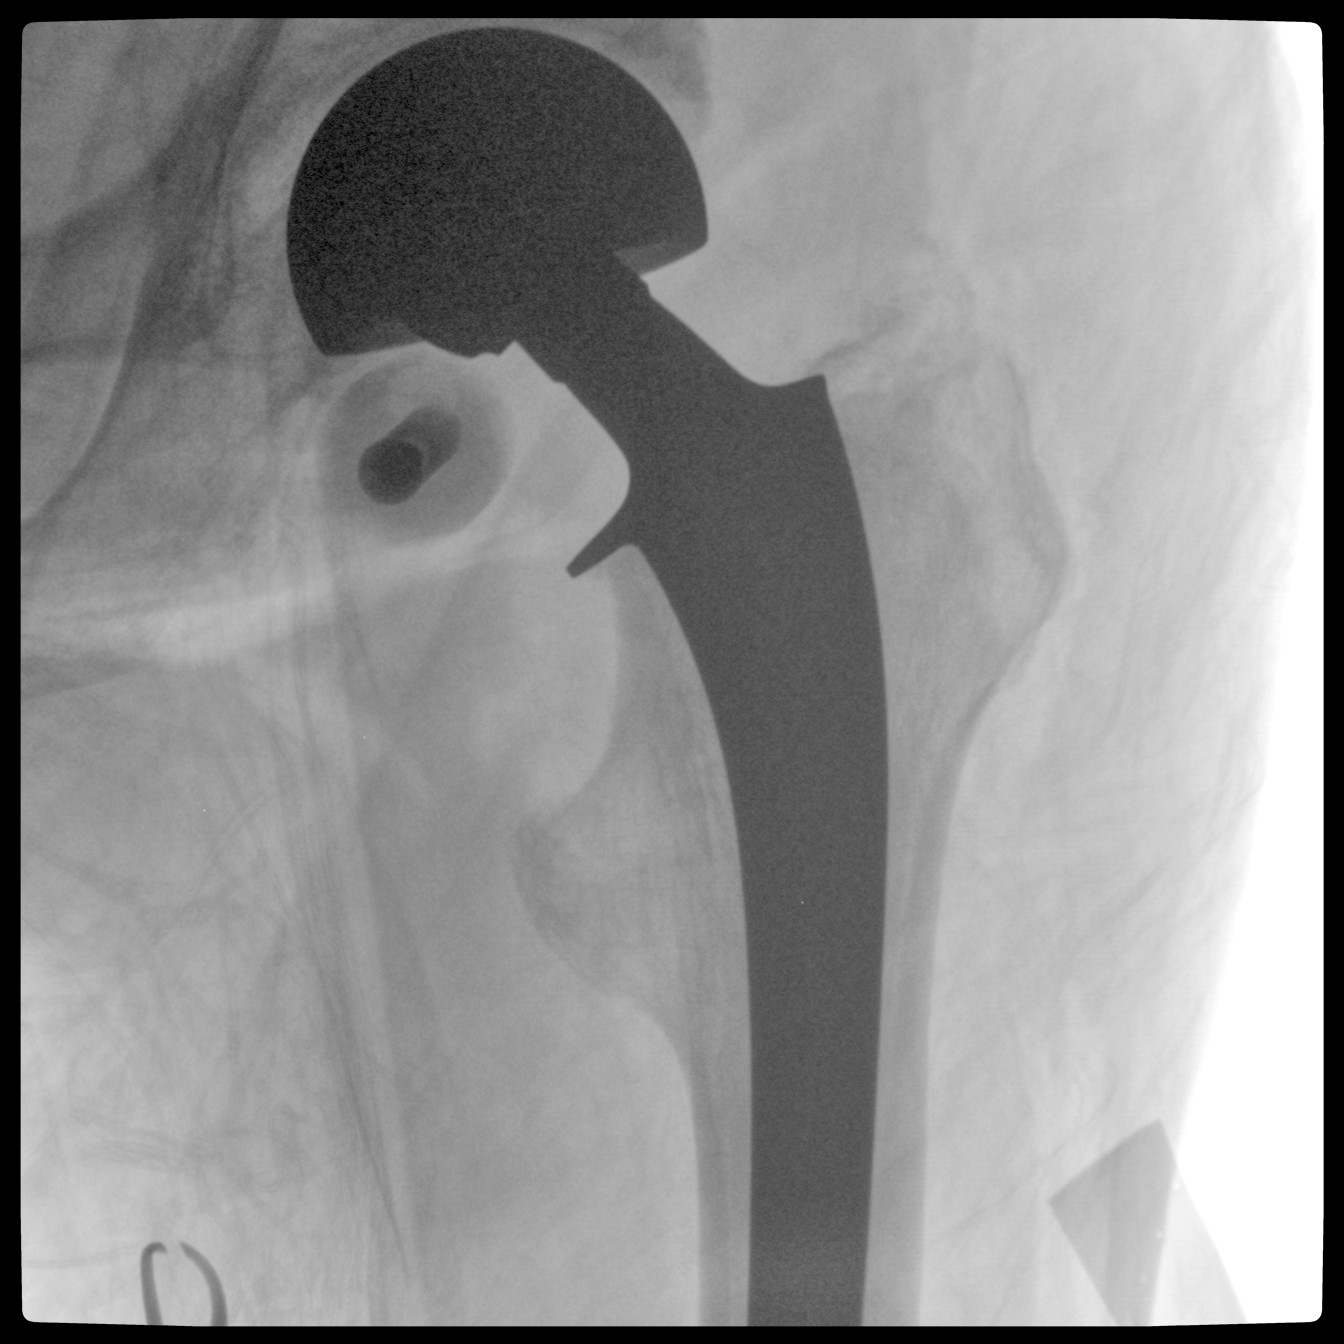

PLX118F-Plus配备了两种平板尺寸,大尺寸动态平板探测器成像面积较传统平板探测器提升了25%以上,在视野需求大的手术中,便于医生更好定位病灶点,规划手术方案,减少因视野范围不足而多次透视、点片造成的不便,不仅提高了手术效率,也减少了辐射剂量。